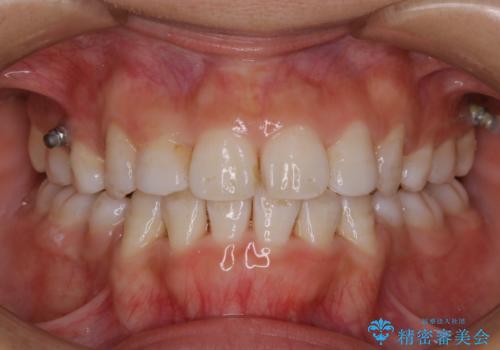

全体的に着色がついていました。

歯の面に凹凸があるため、着色が付きやすい患者様です。1-2カ月に1回のペースでクリーニンングを行っています。